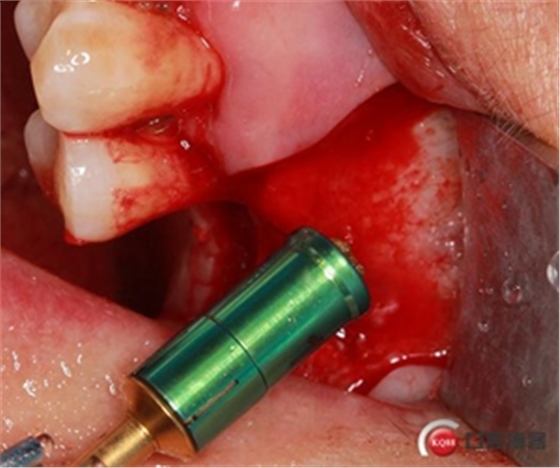

開孔鉆上安裝1mm停止環(huán)。

開窗位置鉆入1mm深度,未能穿透骨壁。

更換2mm停止環(huán)。

穿透上頜竇頰側骨壁,由于擴孔鉆鉆頭特殊的設計形態(tài)

轉速雖快但不會穿破上頜竇膜。